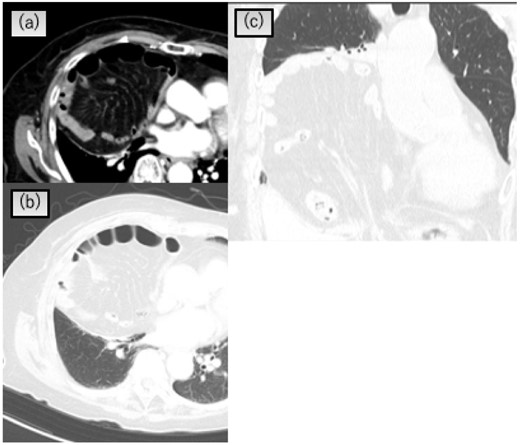

An 89-year-old woman presented to our department for a positive stool guaiac test. Laboratory investigation, including tumor markers, yielded unremarkable results. Colonoscopy revealed a mass in the ascending colon. Computed tomography (CT) revealed a thickening of the ascending colon and a Morgagni-type hernia with the transverse colon and small intestine trapped in the chest, causing atelectasis of the right lower lobe (Fig. 1a, b, c). The size of the hernia orifice was 48 × 40 mm.

Chest CT scan showing that the transverse colon and greater omentum in the right pleural cavity and atelectasis of the right lower lobe. (a) and (b) Axial view, (c) coronal view.